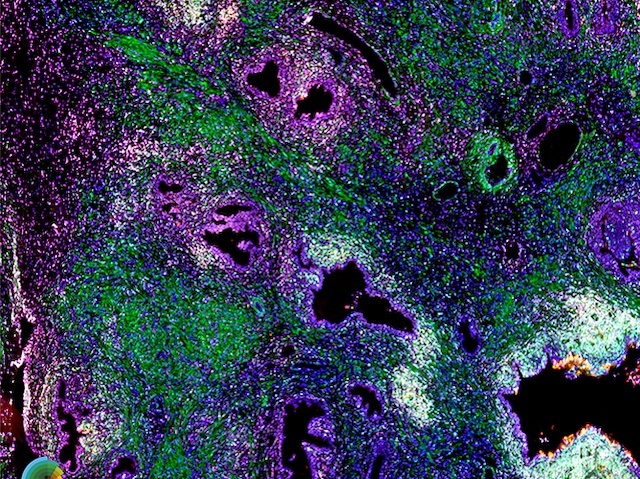

Collagen Creators

As men get older, nightly trips to the loo become more common. For some, it's because of lower urinary tract dysfunction (LUTD). It’s caused by inflammation of the prostate. This leads to prostate fibrosis, that is, the build-up of collagen. To help develop treatments for this stiffer, scar-like tissue, researchers tried to identify the cells needed for collagen production here. They genetically labelled and tracked suspected collagen-producing cells – based on previous research – in mouse prostates, which were inflamed by infecting them with E.coli. As expected, infection led to increased collagen production but only in some of the tracked cells. These cells were fibrocytes and they were also identified in inflamed human prostate samples visualised via fluorescence microscopy (pictured, cells concurrently stained green, magenta and white). These fibrocytes were found in the same regions where collagen accumulates in the prostates of men with LUTD, betraying their likely involvement in the development of fibrosis.